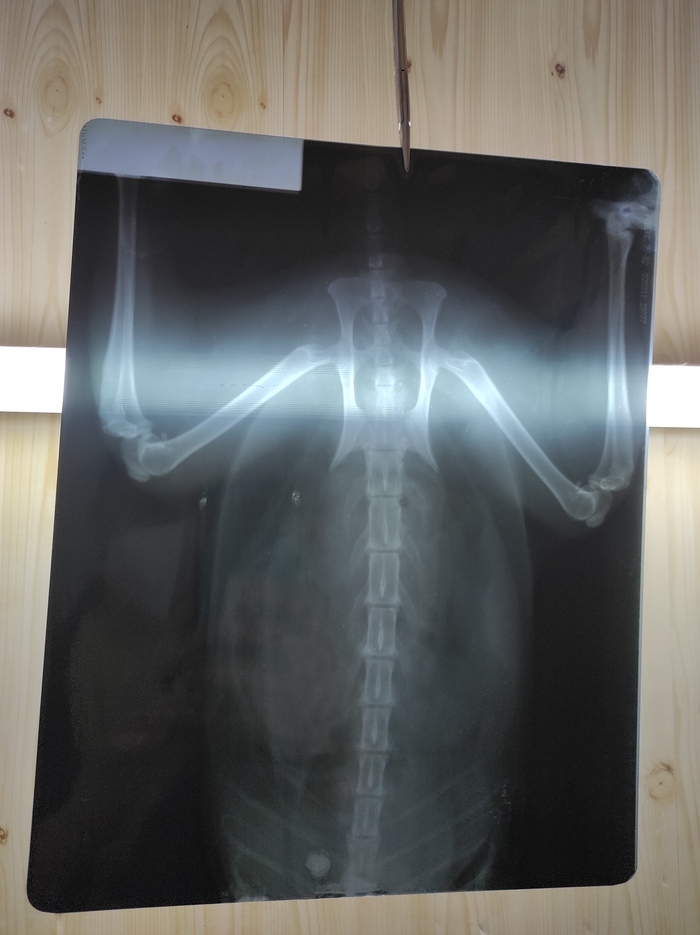

Кошке сломали рёбра

Привет, Пикабу. Кошке на даче (закрытая территория СНТ) какая-то тварь сломала рëбра. Судя по характеру травмы, ударили ногой. Были у ветеринара, там поставили укол обезболивающий. Завтра на повторный приëм. Из рекомендаций - покой и не трогать её, следить, чтобы не стала грудная клетка надуваться. Правильно ли сказали, что лечения как такового нет? Чего вообще ожидать и к чему готовиться? Очень вялая сейчас и плачет постоянно. Буду рада советам ветеринарным. Спасибо

UPD:

Только приехали от врачей. Помогал весь коллектив клиники. На рентгене видна гематома в месте удара, на животе синяк. Сломаны хрящи рëберные, немного воздуха под кожу вышло. Сделали тугую повязку, поставили уколы. Клетку для кроликов уже заказали, будет в ней жить ближайшее время. Состояние стабильное, прогнозы хорошие, а дальше видно будет.

И прошу вас, хватит ругани по поводу выгула кошек. Вы не сможете друг друга переубедить. Всем добра и спасибо за советы, они правда помогли!